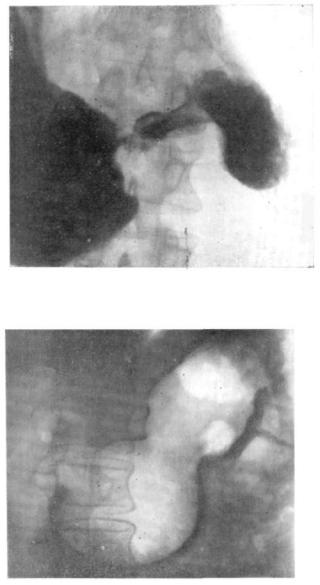

Современные технологии в медицине: рентгенодиагностика заболеваний желудка